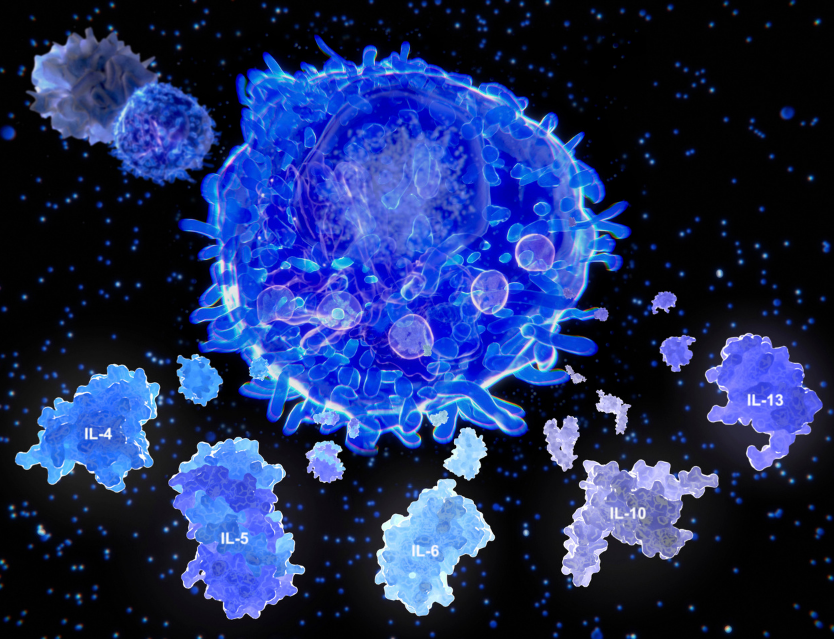

- -Inflamación neurógena (propia del nervio): a través de los nociceptores se genera en sentido eferente una vasoactividad y la consecuente vasodilatación, edema, implicación del sistema de defensa; mastocitos, leucocitos, etc.